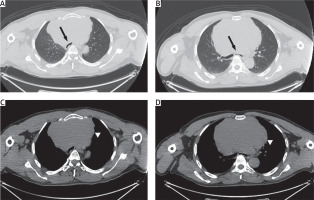

The majority of patients with mediastinal cysts or tumors are symptomatic [8, 9]. In the Çakan et al. [9] study, 83% of the patients were found to be symptomatic. They may come with different symptoms depending on the location of the tumor. The most common findings are compression of the surrounding organs. Findings such as shortness of breath, hoarseness, dysphagia, or chest pain can be detected. As a result of tracheal compression, we can see a flattening in the spirometry curve revealing a plateau sign [10]. In our patient with a diagnosis of primary anterior mediastinal seminoma, severe tracheal and bronchial compression was present (Figure 1) and there was a plateau sign in spirometry. In our study, 80.2% of our patients were symptomatic and were admitted to hospital due to dyspnea (38.4%).

Figure 1

A, B – Parenchymal window of the thorax CT showing compression of the mass to the trachea and the main bronchi (arrows). C, D – The mediastinal window of the thorax CT showing a mass of about 15 cm in the anterior mediastinum (arrowhead)